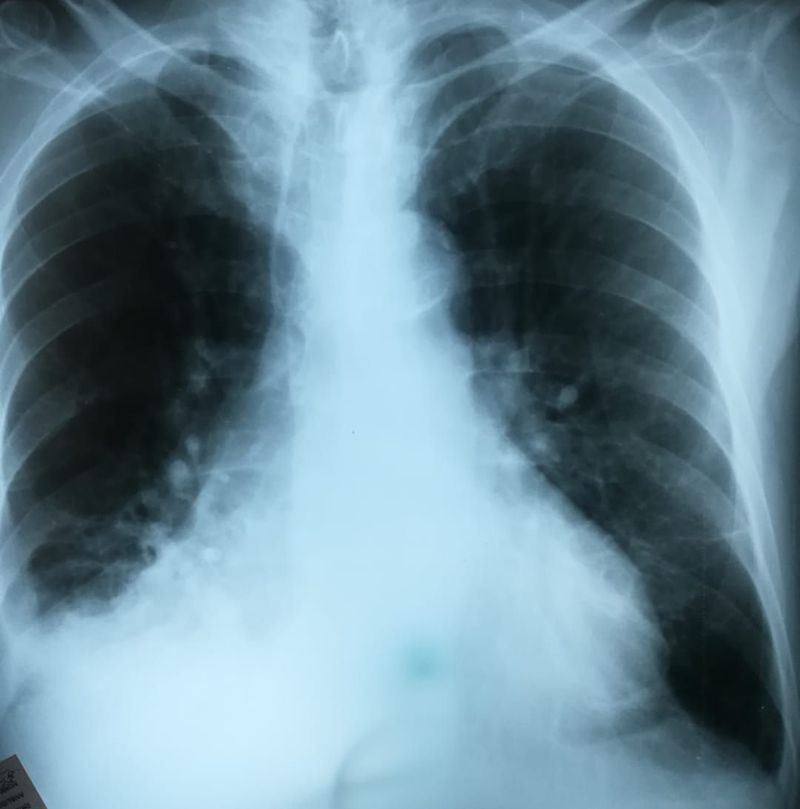

67 Year old male patient, came to the clinic complaining of shortness of breath, orthopnea since 4 days ago, he denies any fever, weight loss or night sweats. his CXR shows obliteration of the right costophrenic angle due to pulmonary effusion. multiple nodules are noted as well. whats your differential diagnosis?